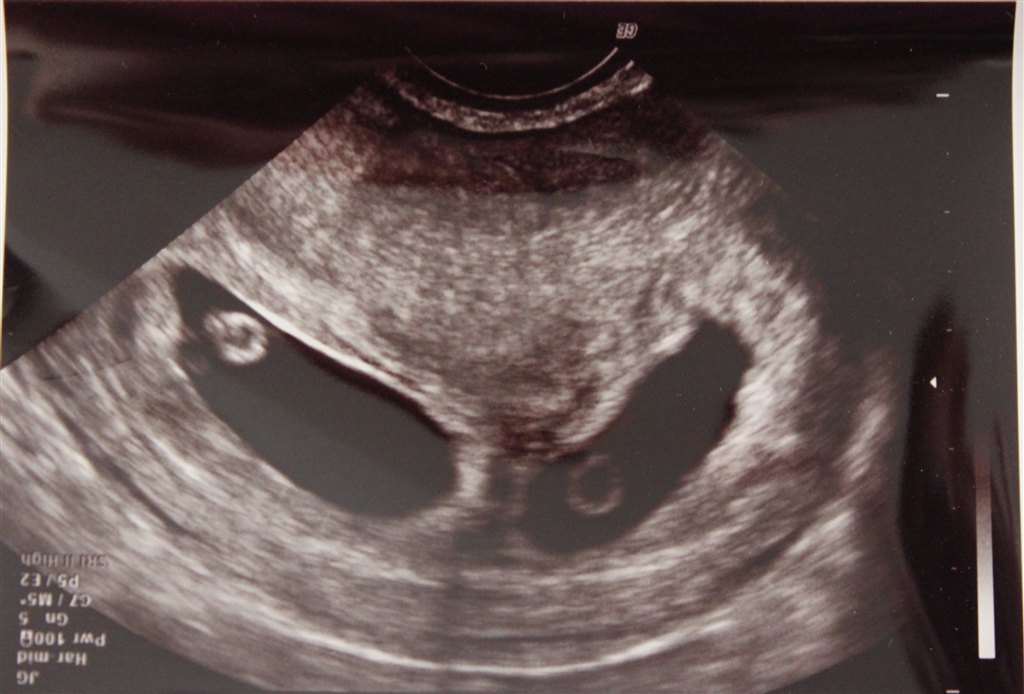

Jeg var til scanning, da jeg var 7+1 (se de vedhæftede billeder).

Den ene af mine havde gemt sig lidt, så den er lidt utydelig

Vedhæftede fotos (klik for at se i fuld størrelse)